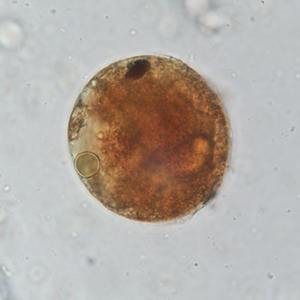

Parasitic cysts are spherical to ovoid and measure 50 to 100 µm in diameter. Their outer membrane is thick, and they have a granulomatous content. A macronucleus and a micronucleus are present, but often difficult to visualize (Strait et al., 2012). Lugol staining allows the visualization of some organelles, which are colored in dark brown. It also allows the coloration of the outer membrane in brown and of the inside of the cyst in cream.